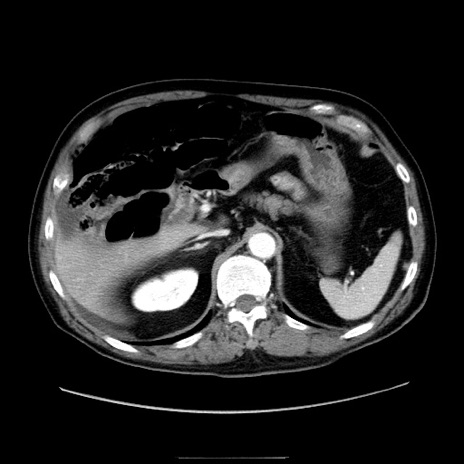

症例30(横断像)

冠状断像

【症例】80歳代男性

【現病歴】約6時間前から臍下部痛が出現。次第に腹部膨隆・背部痛も生じてきたため来院。背部痛の場所は変化しない。

【身体所見】意識清明、BT 36.3℃、BP  131/87mmHg、P 87bpm、SpO2 100%(RA)、臍周囲自発痛・圧痛あり、反跳痛なし、自発痛部位に一致して板状硬あり、腹部膨隆、腸雑音減弱、CVA tenderness両側陰性。